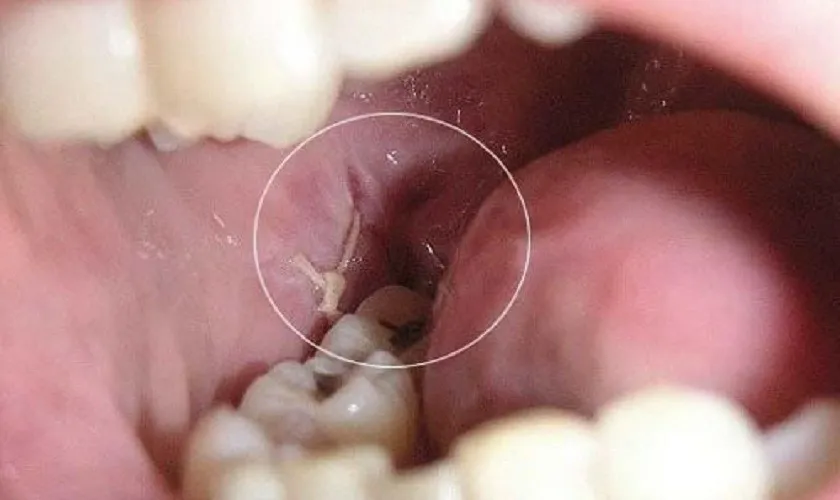

Trước khi tìm hiểu về việc xuất hiện màng trắng sau khi nhổ răng thì cần biết rõ về hiện tượng này. Sau khi nhổ răng, một lớp màng màu trắng thường hình thành tại vị trí ổ răng. Đây là hiện tượng sinh lý bình thường trong quá trình lành thương. Lớp màng này được cấu tạo chủ yếu từ các sợi fibrin – sản phẩm của quá trình đông máu. Đồng thời sợi Fibrin này cũng được kết hợp cùng với các tế bào máu. Tất cả cùng phối hợp với mô hạt và mạch máu đang trong giai đoạn tái tạo.

Vai trò chính của màng trắng là tạo thành một hàng rào bảo vệ tạm thời. Thông qua đó ngăn chặn sự xâm nhập của vi khuẩn và các tác nhân gây hại. Những tác nhân này bắt nguồn từ môi trường miệng vào vùng mô đang tổn thương. Đồng thời, lớp màng này hỗ trợ quá trình hồi phục mô bằng cách duy trì môi trường ổn định. Cùng với đó là thúc đẩy sự tăng sinh tế bào và hình thành mô mới. Tất cả sẽ giúp vết thương sau nhổ răng lành nhanh chóng và hiệu quả.

- Tiếp theo, các tế bào mô liên kết, mao mạch và sợi fibrin dần hình thành và liên kết. Từ đó tạo nên một lớp màng màu trắng đục, phủ kín ổ răng.

- Lớp màng này không phải là mủ hay hoại tử, mà là màng sinh học bảo vệ. Nó đóng vai trò như một “lá chắn” ngăn vi khuẩn, thức ăn và tác động bên ngoài. Hạn chế xâm nhập vào mô đang tổn thương.

Mô hạt thường có màu trắng hoặc trắng ngà. Do đó rất dễ bị nhầm lẫn với các hiện tượng bất thường khác tại ổ răng. Đặc biệt là xuất hiện màng trắng sau khi nhổ răng khi quan sát thấy bằng mắt thường. Thực tế, trong giai đoạn lành thương, sự hiện diện của màng trắng do mô hạt hình thành là hoàn toàn bình thường và không gây hại. Đây là phản ứng sinh lý tự nhiên. Nó cho thấy cơ thể đang tiến hành quá trình phục hồi.